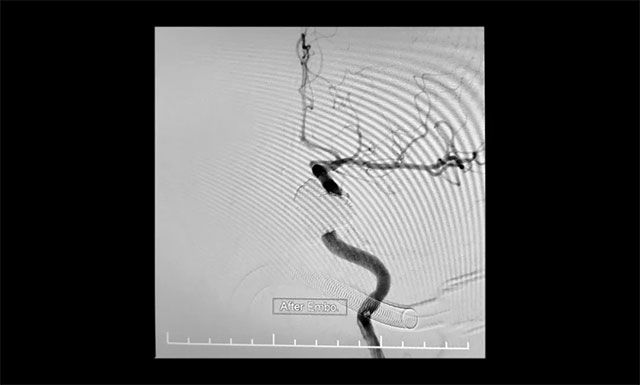

▲ 术中造影证实瘘口均完全闭塞

“钢筋混凝土技术”操作时需十分谨慎,若注胶不足会导致瘘口封闭不全症状不缓解,而注胶不慎又会导致胶溢入颈内动脉,造成颈动脉堵塞致大面积脑梗塞的灾难性后果。术中,张琪博士在李喆医生、周林华医生协助下先将海绵窦内小心填入13枚大直径弹簧圈作为“钢筋骨架”,然后准确地将球囊置于瘘口处的颈内动脉内,缓慢充盈球囊将瘘口暂时与颈内动脉隔离,然后小心翼翼地向瘘口内注入onyx胶封堵,并仔细观察胶的反流和扩散情况。该方法每次球囊阻断颈内动脉的时间不能超过6分钟,否则将可能导致脑缺血。“1分钟、2分钟、3分钟……”最终,经过几个循环的封堵,瘘口被栓塞得严严实实,在确认瘘口及主要异常回流途径完全闭塞后,及时终止手术,取得了较好的临床效果,术中造影证实瘘口均完全闭塞。